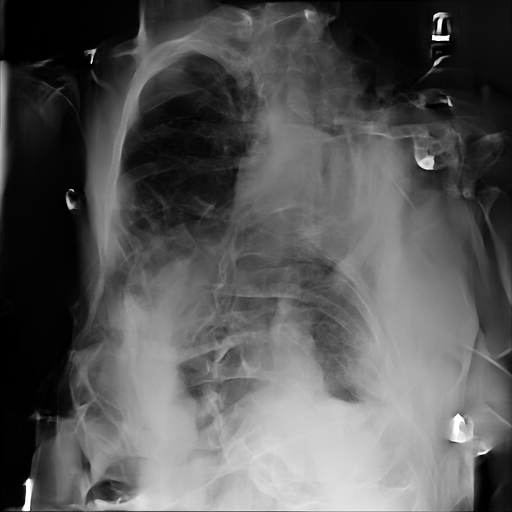

Refer to caption

case 1

Figure 2: ϵitalic-ϵ\epsilon-LDP-processed CXR images obtained with DP-GLOW.

In Fig. 1, we show four ϵitalic-ϵ\epsilon-LDP-processed CXR images of clinical cases obtained with the image domain LDP, which directly imposes the Laplace mechanism on the input image, with different privacy budgets together with the original images. Fig. 2 shows four ϵitalic-ϵ\epsilon-LDP-processed CXR images of clinical cases obtained with DP-GLOW and different privacy budgets together with the original images. In case 1 for DP-GLOW, there is decreased permeability in the bilateral hilar regions. Although this hilar opacity tends to be preserved with a larger privacy budget, the entire image is degraded when the privacy budget becomes 101HWsuperscript101𝐻𝑊10^{1}\cdot H\cdot W. A similar tendency is observed in the images of all the four cases for DP-GLOW; for example, in case 4 with ϵ=101HWitalic-ϵsuperscript101𝐻𝑊\epsilon=10^{1}\cdot H\cdot W, the lung opacity suggesting pneumonia in the right lower lung field is well preserved, while the entire image is degraded.